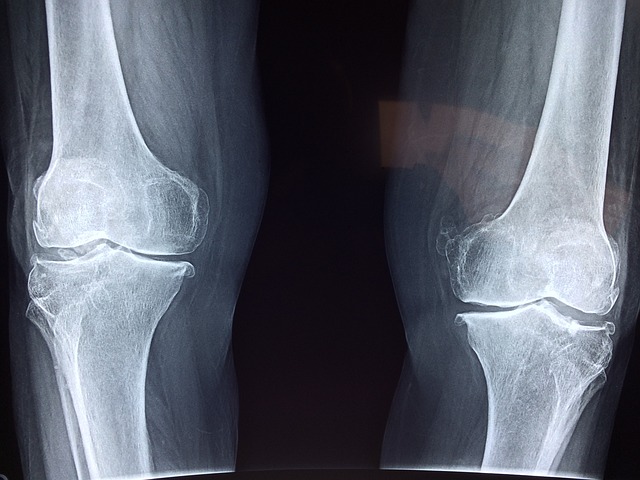

- X-레이: 슬개골과 대퇴골 사이의 정렬 상태를 평가하고, 뼈의 구조적 문제가 있는지 확인합니다. 그러나 X-레이는 연골 자체는 보여주지 않습니다.